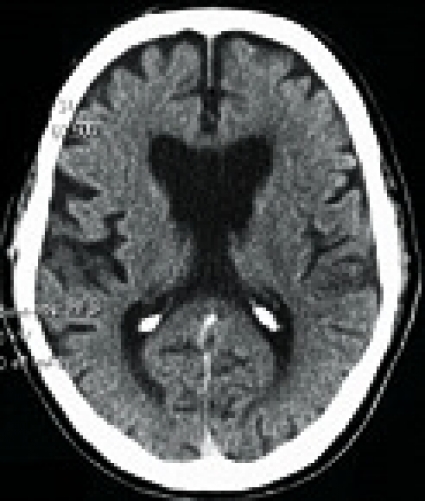

Hjärnavbildning. På datortomografi (DT) och magnetisk resonanstomografi (MRT) kan akuta hjärnskador vid boxning, tex subduralhematom (Figur 2 [upp till höger]) diagnostiseras. Vid CTBI-B är de vanligaste fynden på DT och MRT en ospecifik kortikal och/eller cerebellär atrofi (Figur 2 [ned till vänster]), vidgade ventriklar och fynd av cavum saepti pellucidi (CSP)[32]. I den största DT-studien, som inkluderade 338 proffsboxare, fann man måttlig atrofi hos 7 procent och lätt atrofi hos 22 procent [21]. Mer än lätt atrofi är således ett ovanligt fynd. Även med MRT är det vanligaste fyndet hos professionella boxare en ospecifik atrofi [33]. Värdet av DT och MRT vid utvärdering av kronisk hjärnskada hos boxare är således begränsat.